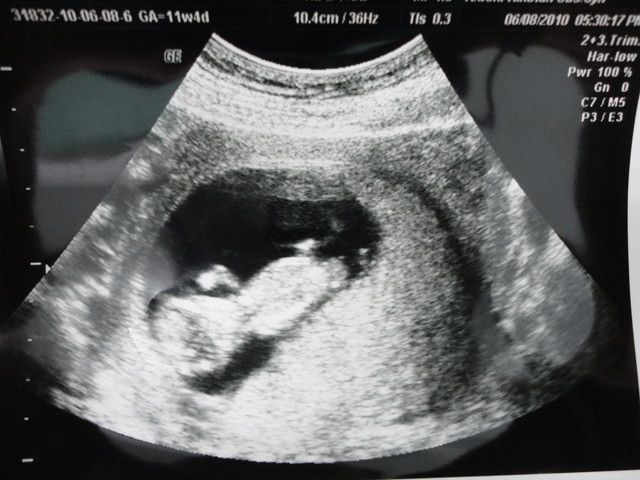

但這次有點不同的是,先進來做檢查的是一位小姐,而且她還看了蠻久的

我跟老公最注意的應該就只有螢幕上顯示出胎兒大小

看到兩個都有1500以上,感覺還蠻開心的

直到那位測試員跟在隔壁看另一個人的我的主治醫師說:「醫師,跟剛剛的雙胞胎一樣」

操作員指著螢幕上的某個點,主治醫師則面色凝重

沒多久,醫生說:「右邊的這個因為自己的臍帶打結,養分無法通過而沒心跳了!」

醫師說:「是的,但是因為她是兩個羊膜腔,使用不同的胎盤,所以就算一個沒心跳,另一個還是可以繼續待在腹中成長」

「但是妳的是單一羊膜腔,而且共用一個胎盤,所以沒心跳的胎兒一定會影響到還活著的胎兒,至於多久才會影響到,沒有辦法估計」